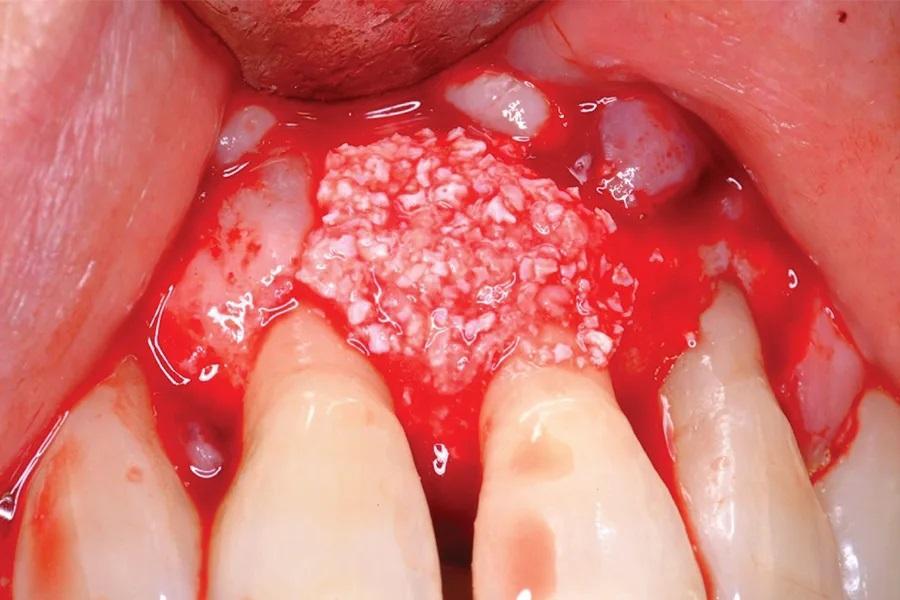

Фото 5. Трансплантационный материал был приготовлен путем комбинирования ДМБК, концентратов тромбоцитов и аутогенных костных стружек с кальцием и тромбином для индукции коагуляции.